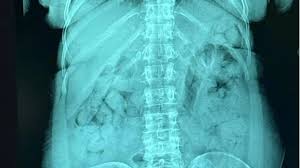

İtaliyanın Berqamo şəhərinin hava limanında hüquq-mühafizə orqanlarının əməkdaşları mədəsində 120 heroin kapsulunu keçirməyə cəhd göstərən 46 yaşlı rumınəsilli qadını saxlayıblar.

Berqamodakı xəstəxanada aparılan rentgen müayinələri qadının ümumi çəkisi 1.393 kq heroin olan 120 plastik kapsul udduğunu təsdiqləyib.

Kapsullar götürüldükdən sonra narkotik vasitə müsadirə edilib, qadın isə həbs edilərək Berqamo həbsxanasına yerləşdirilib.